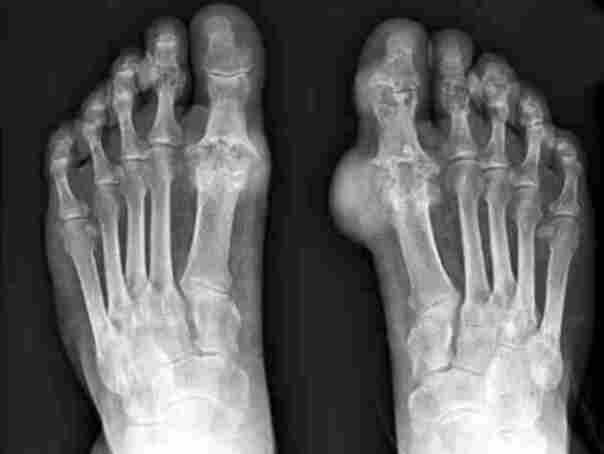

Health গেঁটেবাত ও অ্যালোপিউরিনল: হঠাৎ তীব্র যন্ত্রণা ও প্রতিরোধের উপায় March 14, 2025April 30, 2025 গেঁটেবাত কেন হয়, কিভাবে শনাক্ত করবেন এবং কীভাবে প্রতিরোধ করবেন? ১৫ মার্চ, ২০২৫ গেঁটেবাত (Gout)… Read More